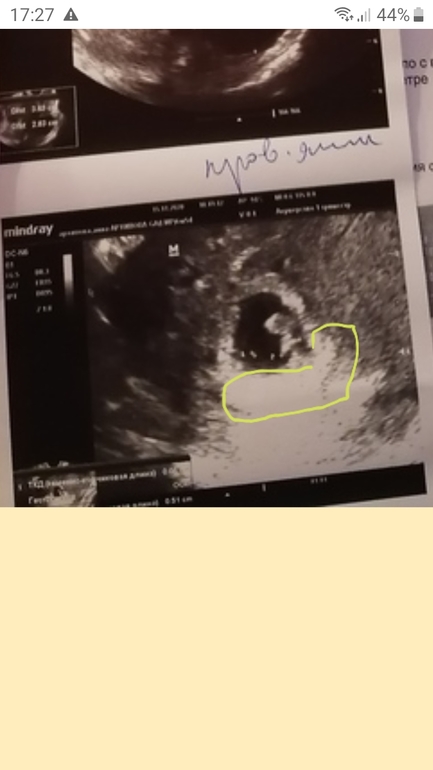

Оль, я уже не верю ничему. Вот смотри моё узи в 6.5 это одно узи, только разные ракурсы.

Я видела, но по тому фото не понятно где плацента, Аманда сотней смотреть, а не по хориону

Вы молодцы рискнули. По Рамзи у вас мальчик, если вагинальный датчик был🙈.

НЮША (ник в ИГ Visla79), а если хорион справа, то кто? Врач вроде сказал, что справа прикрепился) Запуталась я с этим Рамзи и никак понять не могу. Вот кто у нас? Датчик наружний